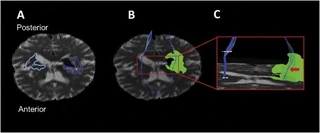

BACKGROUND: The impact of perihematoma edema in Intracerebral Hemorrhage (ICH) on white matter integrity is uncertain. Fractional Anisotropy (FA), as measured with Diffusion Tensor Imaging (DTI), can be used to assess white matter microstructure. We tested the hypotheses that sections of the Corticospinal Tract (CST) passing through perihematoma edema would 1) have low FA relative to the contralateral CST and 2) would predict NIHSS motor score in ICH patients. METHODS: Patients were prospectively imaged with DTI at 48h and 7days after onset. Edema volume/extent was measured on CT at baseline and 24h. FA, mean, axial and radial diffusivity were measured in the perihematoma edema, contralateral CST and sections of CST passing through the edema (’edematous CST’). RESULTS: Patients (n=27, mean age 67textpm 13) were scanned with DTI at a median (IQR) of 42.3 (24.5) hours and 7.7 (1.8) days from onset. Median acute ICH volume was 8.8 (22) ml. FA in edematous CST at 72h was decreased (0.37textpm 0.03) relative to contralateral CST (0.52textpm 0.06; p$<~$0.0001). Day 7 FA in edematous CST (0.35textpm 0.08) was also decreased compared to contralateral CST (0.54textpm 0.06; p$<~$0.0001). FA remained stable between 72h (0.37textpm 0.03) and day 7 (0.35textpm 0.07; p=0.350). FA at 72h ($h̊o~$=-0.22, p=0.420) and day 7 ($o̊~$=-0.14, p~=~0.624) was unrelated to 90-day motor score. CONCLUSIONS: FA is decreased in the CST where it passes through the edema. Decreased FA in the edematous CST remained stable over time, was unrelated to motor score, and may represent water infiltration into the tracts rather than axonal injury.